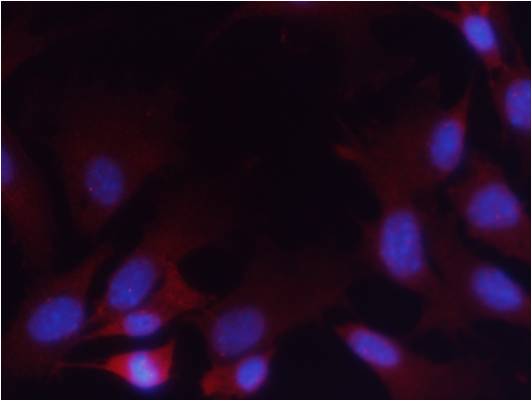

Immunofluorescence staining of methanol-fixed Hela cells using PTEN(Phospho-Ser380/Thr382/Thr383) Antibody #11056.